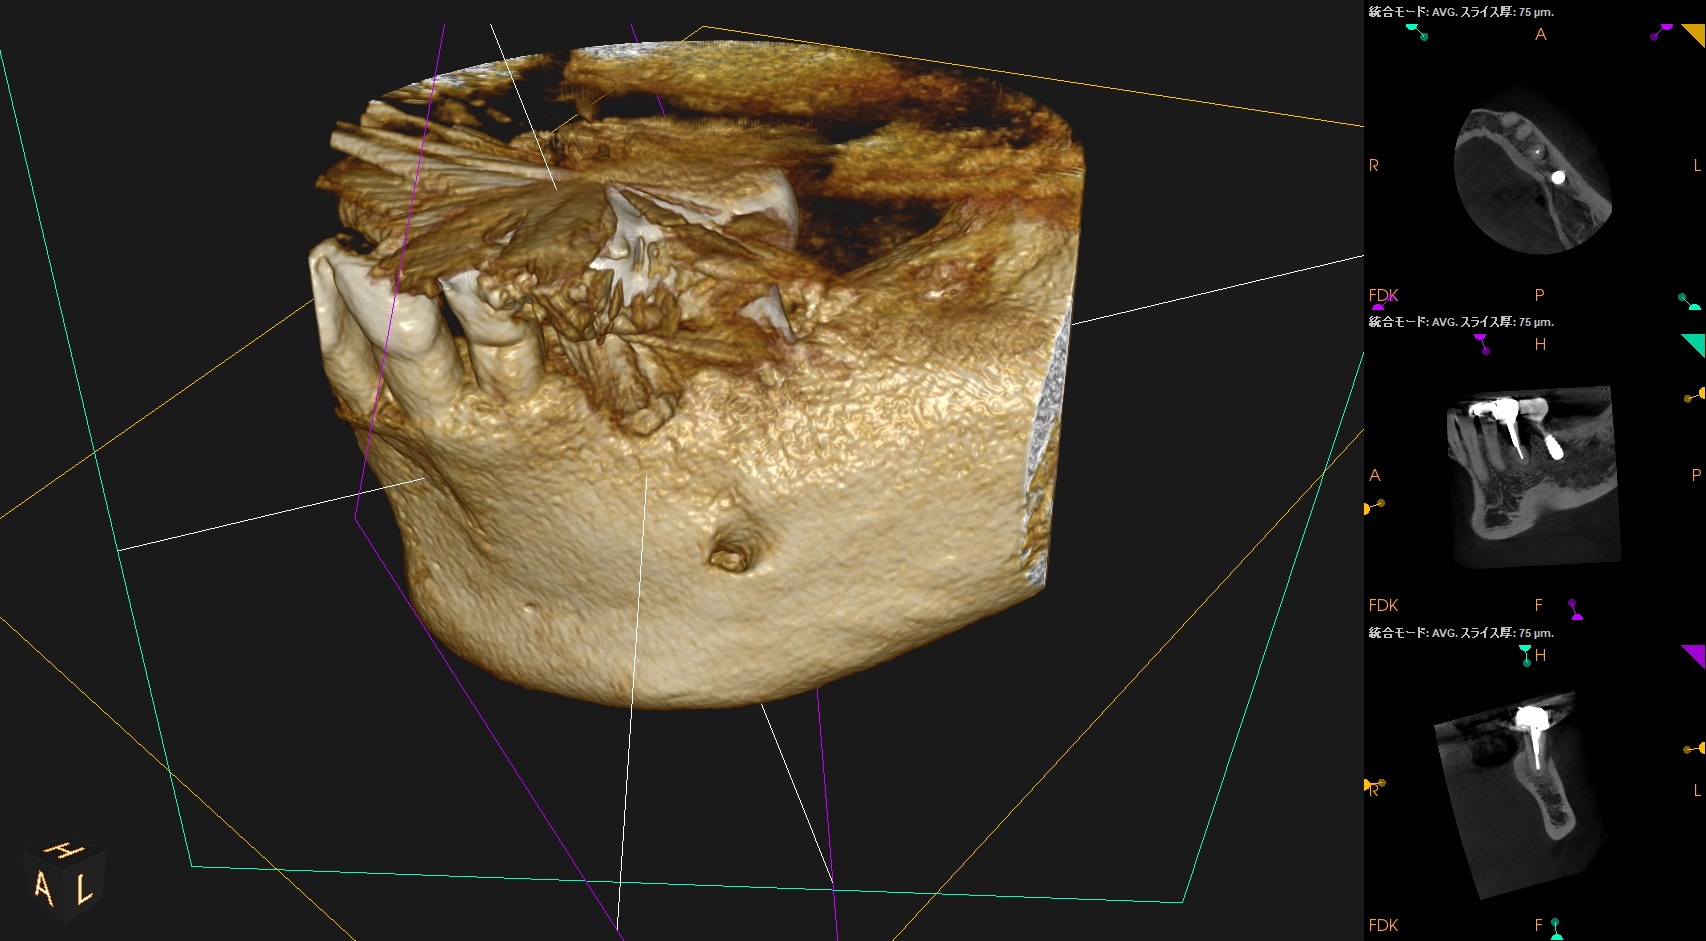

頬側の皮質骨は既にない。

VRFを想像させる絵だが、

術前の歯周ポケット測定では、#20は全周、Within Normal Limit(正常の範囲内)である。

術後にPA, CBCTを撮影した。